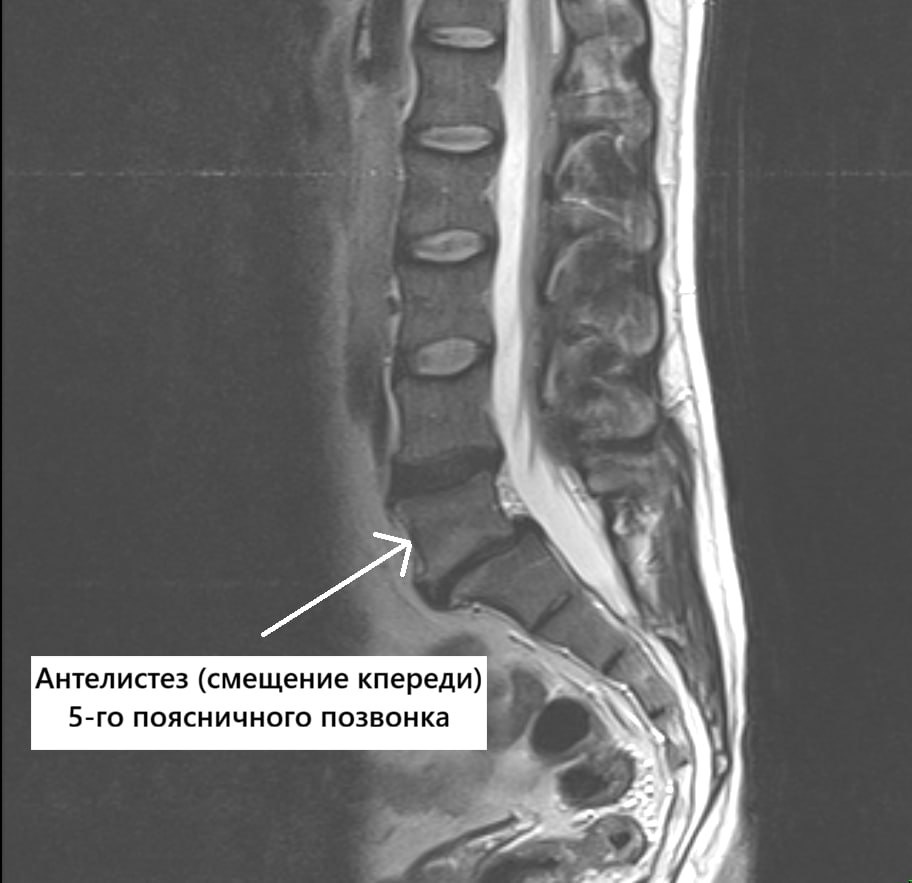

ΠŸΠ°Ρ†ΠΈΠ΅Π½Ρ‚Ρƒ Π±Ρ‹Π»ΠΎ Π²Ρ‹ΠΏΠΎΠ»Π½Π΅Π½ΠΎ МРВ поясничного ΠΎΡ‚Π΄Π΅Π»Π° ΠΏΠΎΠ·Π²ΠΎΠ½ΠΎΡ‡Π½ΠΈΠΊΠ°.

Π Π΅Π·ΡƒΠ»ΡŒΡ‚Π°Ρ‚Ρ‹ МРВ пояснично-крСстцового-ΠΊΠΎΠΏΡ‡ΠΈΠΊΠΎΠ²ΠΎΠ³ΠΎ ΠΎΡ‚Π΄Π΅Π»Π° ΠΏΠΎΠ·Π²ΠΎΠ½ΠΎΡ‡Π½ΠΈΠΊΠ°.

По Ρ€Π΅Π·ΡƒΠ»ΡŒΡ‚Π°Ρ‚Π°ΠΌ исслСдования выявлСны:

🏁 ΠΏΡ€ΠΎΡ‚Ρ€ΡƒΠ·ΠΈΠΈ ΠΌΠ΅ΠΆΠΏΠΎΠ·Π²ΠΎΠ½ΠΊΠΎΠ²Ρ‹Ρ… дисков L4–S1

🏁 антСлистСз Ρ‚Π΅Π»Π° L5 ΠΏΠΎΠ·Π²ΠΎΠ½ΠΊΠ° (смСщСниС ΠΏΠΎΠ·Π²ΠΎΠ½ΠΊΠ° Π²ΠΏΠ΅Ρ€Π΅Π΄ ΠΎΡ‚Π½ΠΎΡΠΈΡ‚Π΅Π»ΡŒΠ½ΠΎ Π½ΠΈΠΆΠ΅Π»Π΅ΠΆΠ°Ρ‰Π΅Π³ΠΎ)

(измСнСния прСдставлСны Π½Π° Ρ„ΠΎΡ‚ΠΎ)